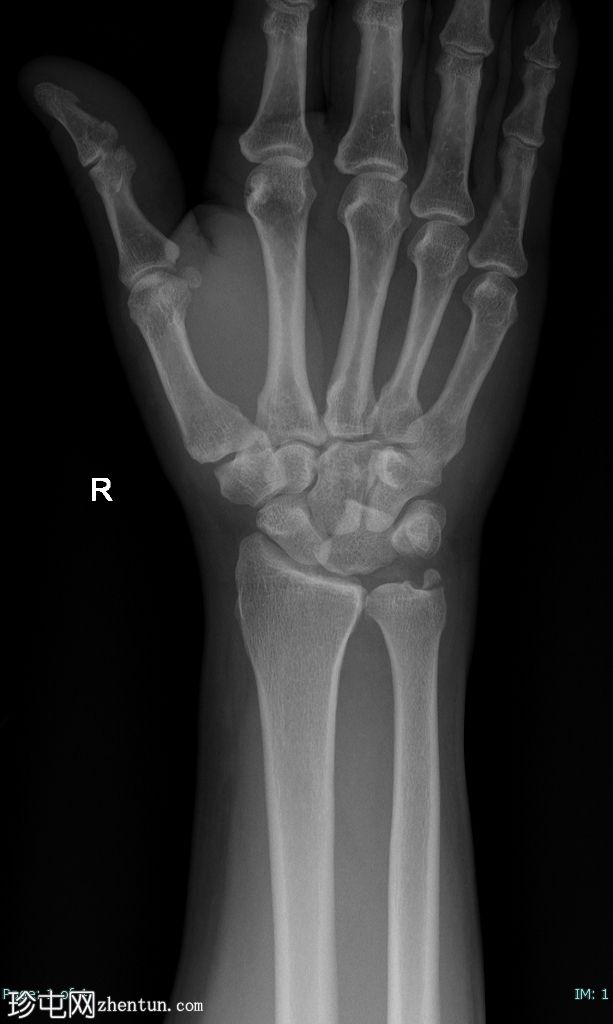

正位片

月骨呈“饼状”移位,掌侧成角和移位,侧位片上呈“倾倒的茶杯”样外观。

尺骨茎突骨折移位。未见其他骨折。

腕关节处桡骨和尺骨对位正常。

软组织肿胀。

这是一个IV期腕骨脱位的典型例子。